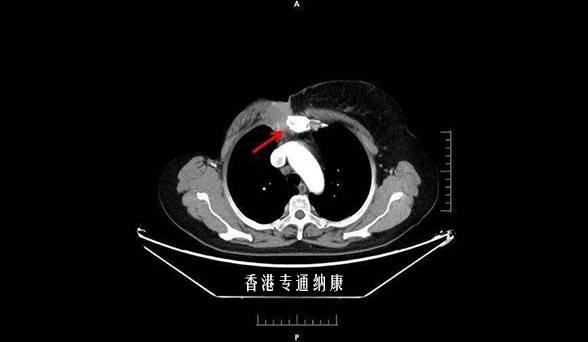

【适应症】多线治疗进展的HER2阳性的晚期乳腺癌;除此,HER2阳性的肺癌、胃癌、结肠癌也可以使用。